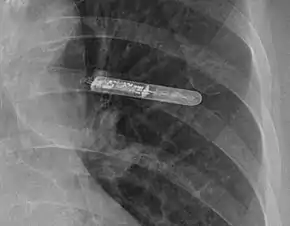

In medicine, a Holter monitor (often simply Holter) is a type of ambulatory electrocardiography device, a portable device for cardiac monitoring (the monitoring of the electrical activity of the cardiovascular system) for at least 24 hours.

When used to study the heart, much like standard electrocardiography, the Holter monitor records electrical signals from the heart via a series of electrodes attached to the chest. Electrodes are placed over bones to minimize artifacts from muscular activity. The number and position of electrodes varies by model, but most Holter monitors employ between three and eight. These electrodes are connected to a small piece of equipment that is attached to the patient's belt or hung around the neck, keeping a log of the heart's electrical activity throughout the recording period. A 12-lead Holter system is used when precise ECG information is required to analyse the exact origin of the abnormal signals.[5]

The size of the recorder differs depending on the manufacturer of the device. The average dimensions of today's Holter monitors are about 110x70x30 mm, but some are only 61x46x20 mm and weigh 99 g.[6]